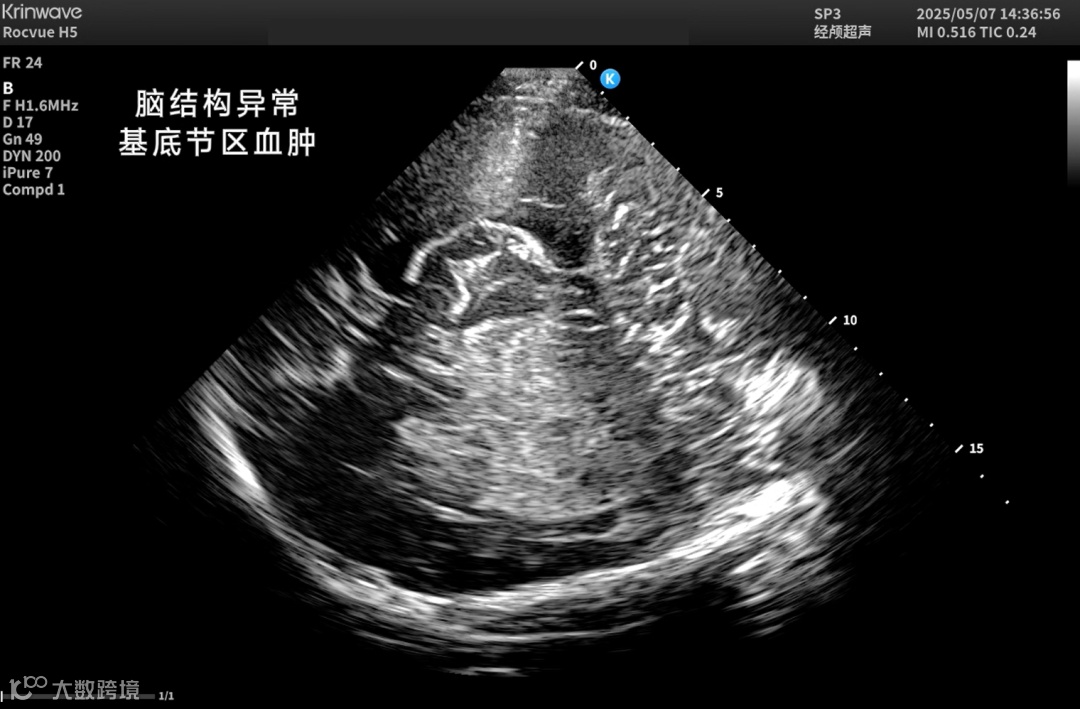

颅脑一直是超声成像的难题——

颅骨厚、衰减强、反射乱,声能传输率不足10%。

让超声在颅脑领域真正“看得见、看得清”。

● 神经重症监测

床旁实时评估颅内压、脑血流动力、脑水肿及血肿变化;